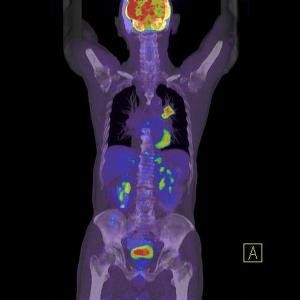

A PET/CT (pozitronemissziós tomográf és egy CT kamera egy készülékben) vizsgálatok nem csak azok számára adnak választ, akik valamilyen rákos megbetegedéssel érkeznek hozzánk, hanem azok számára is, akik szeretnének meggyőződni arról, hogy szervezetükben nincs jelen semmilyen daganat.

A vizsgálat során a szervezetbe intravénásan egy FDG nevű anyagot adunk, (ez egy szőlőcukor molekulához kapcsolt fluor izotóp) amely azután szétterjed a szervezetben, hiszen a sejtek működésük során cukrot használnak fel. A vizsgálati képeken látható színes foltok jelölik azokat a gócpontokat, ahol ez az anyag felhalmozódik, ugyanis a daganatok sokkal több cukrot használnak fel működésük során, ezáltal a fluor is felhalmozódik és a PET kamera ezt érzékeli.

A CT képekre rávetített PET felvételek segítségével nagyon pontosan lokalizálható az elváltozás, valamint annak pontos mérete is meghatározható. A PET/CT akár már 2-3 mm-es állapotában felfedi a daganatos elváltozásokat, ami azért fontos, mert a korai stádiumban a rák nagyon jó eséllyel gyógyítható, ha időben megkezdik a megfelelő kezelést.